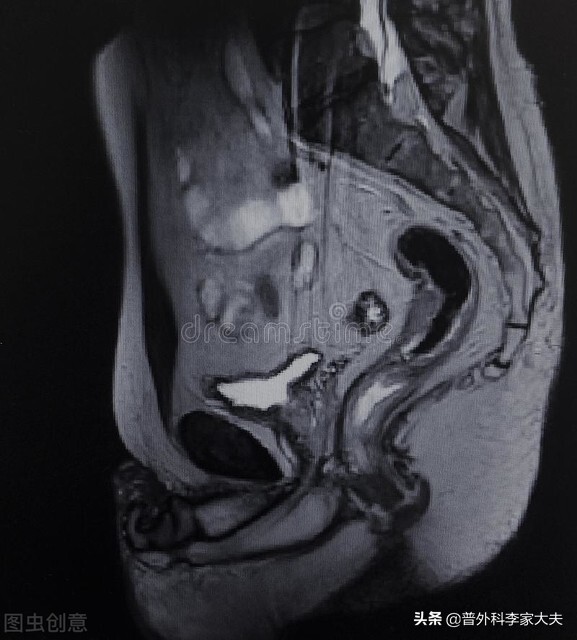

患者的直肠癌大小为3.5cm×3.8cm,从我的临床经验考虑,直肠癌长到这样大的患者,他的直肠癌T分期估计应该是T3或T4分期。再加上患者术后发现有淋巴结转移1/12,我从最理想的情况分析,患者还没有发生远处转移,则患者的直肠癌病理分期应该是T3N1M0或T4N1M0的患者,也就是说患者的直肠癌术后病理分期就是ⅢB直肠癌。而这种类型的直肠癌患者,正是上面介绍的直肠癌术后放疗的适应症患者了。因此,从提高患者术后直肠癌疗效及安全的角度,患者是应该进行直肠癌的术后放疗的。

我就拿今天我回复的这位患者的情况来给大家分析下:由于患者提供的病历资料非常有限,加上我也未看过患者,对患者的很多情况都不了解,比如患者的身体状况如何?是否本身存在放疗禁忌症?是否有其他合并疾病无法耐受放疗?他手术的肛门功能怎样?等等情况我一无所知。